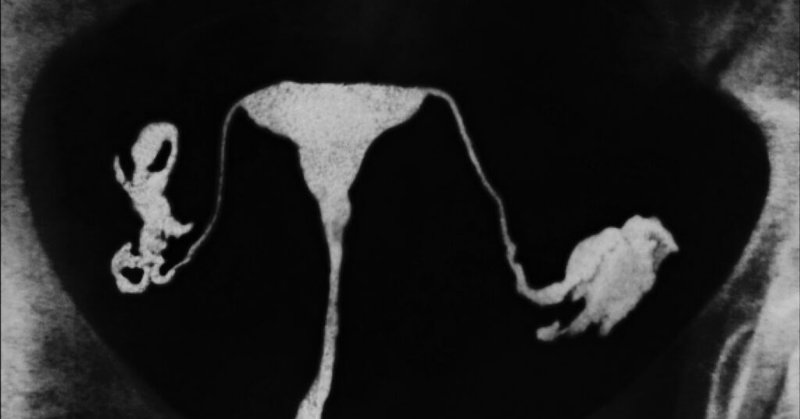

Wrote about how fallopian tube removal has been replacing “tube-tying” — and how pathologists first found evidence that the most common form of ovarian cancer often begins in the tube. https://t.co/hr5d1PVN9Z

statnews.com

To prevent ovarian cancers, fallopian tube removal is on an upsurge — and diagnostic manuals are finally catching up.